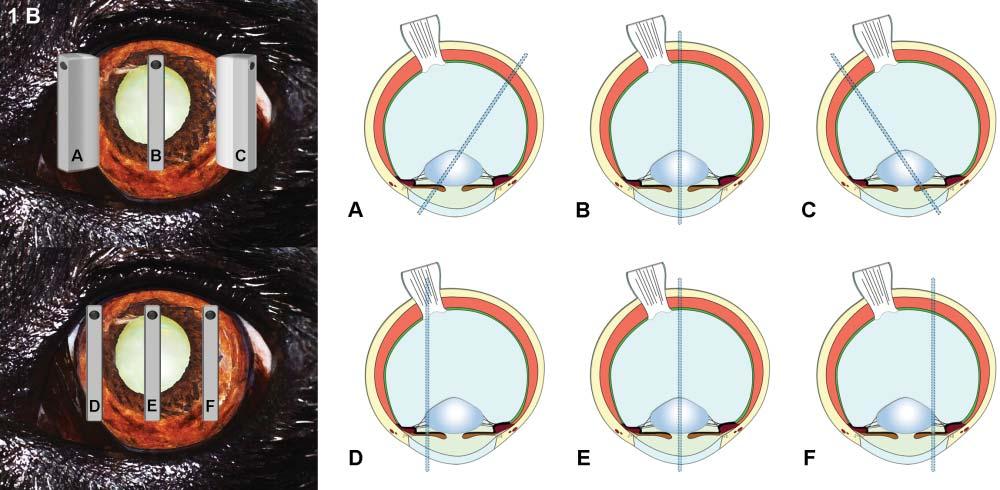

Toproducean image,thefirstpiezoelectriccrystals arestimulatedtogenerateashortultrasoundpulse–comprisingthreetofourwaves–thattravelsthrough tissueinterfacestoproducethousandsofechoes thataresentbacktotheprobe(Figure1.1).Shortly

afterward,anewultrasoundpulseleavestheprobe atadifferentangle,generatinganewsetofechoes thatreturntothesecondseriesofcrystals.Assuminga constantwavepropagationspeedof1,540m/sinsoft tissues,eachoftheseechoescanbelocatedprecisely alongthetrajectory,dependingonthetimeinterval betweenthedepartingwaveandthereturningecho (Hangiandreouetal.2003).Hundredsofwavelinesare producedthisway,scanningtissuesathighspeedto produceover30images/s,eachonecontainingthousandsofpixelsdescribingtheacousticcharacteristics ofthescannedtissues.

Figure1.1. Ultrasoundpropagationandimageformation. Eachultrasoundimageisformedbytheadditionofhundredsofindividualscanlines.Eachlineisproducedaftera singleultrasoundpulse(inyellow)isemittedbythetransducer.Asthispulsepropagatesthroughsofttissues,many echoes(ingreen)aregeneratedatinterfacesofdifferentacousticimpedance(suchashepatocytes–connectivetissue),producinganimageofvariableechogenicityandechotexture. Eachechoisanatomicallylocalizedbasedonthetimeinterval betweentheemittedpulseanditsreception.Afteraspecific time,anewpulseisemittedalonganadjacentline,producing anadditionalscanline.Scanlinesaregeneratedveryrapidly andsuccessively,producing15–60images/s,allowing“real time”ultrasonography.